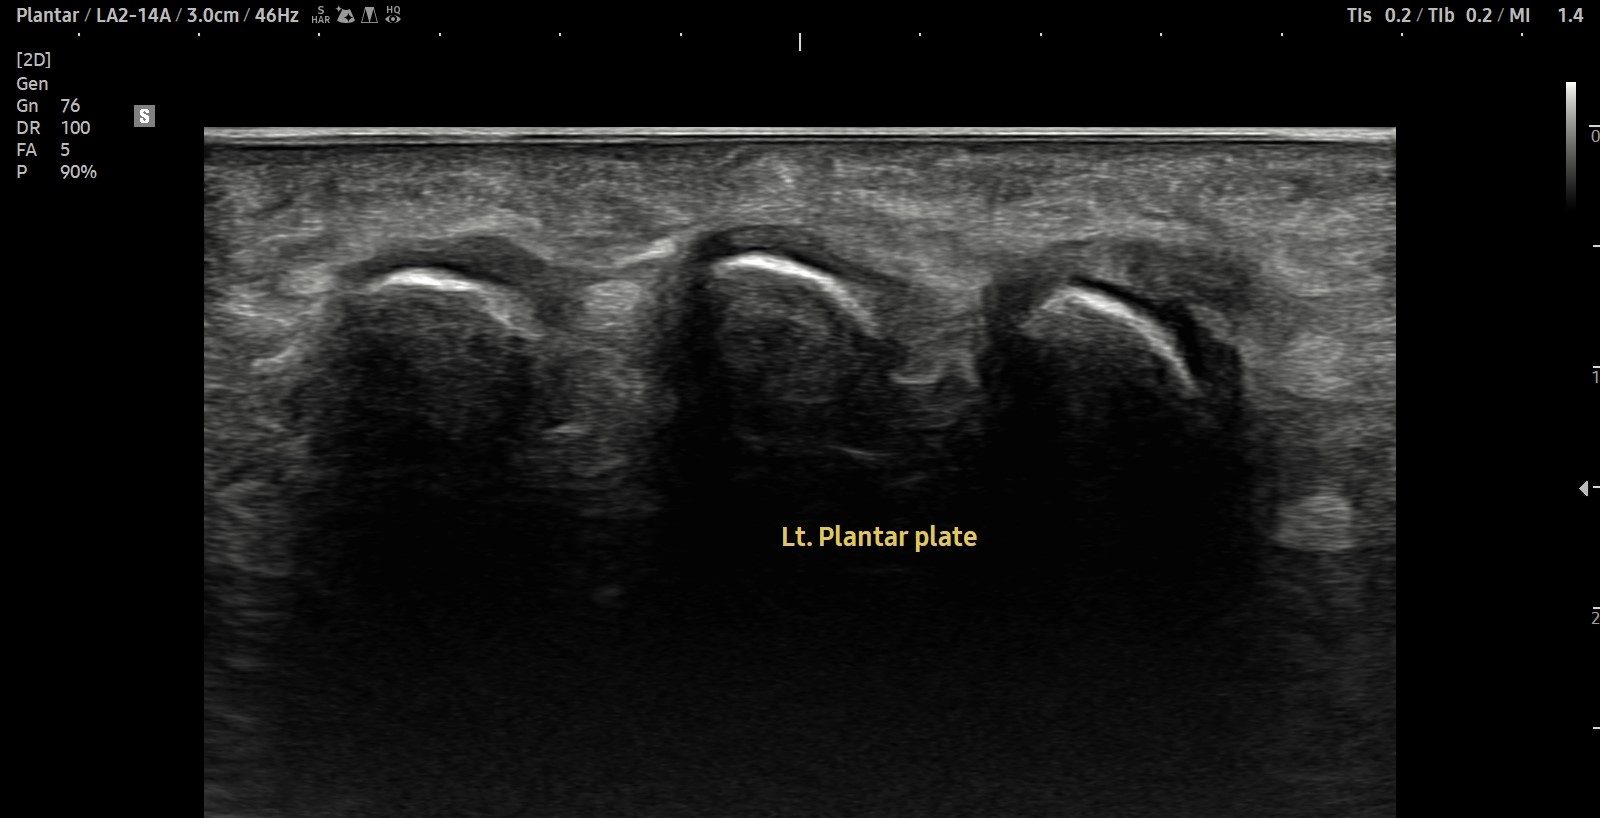

- 치료기간 : 2025. 5. 1. ~ 2025. 6. 14

- 치료횟수 : 10 회

[치료 전]

[치료 후]